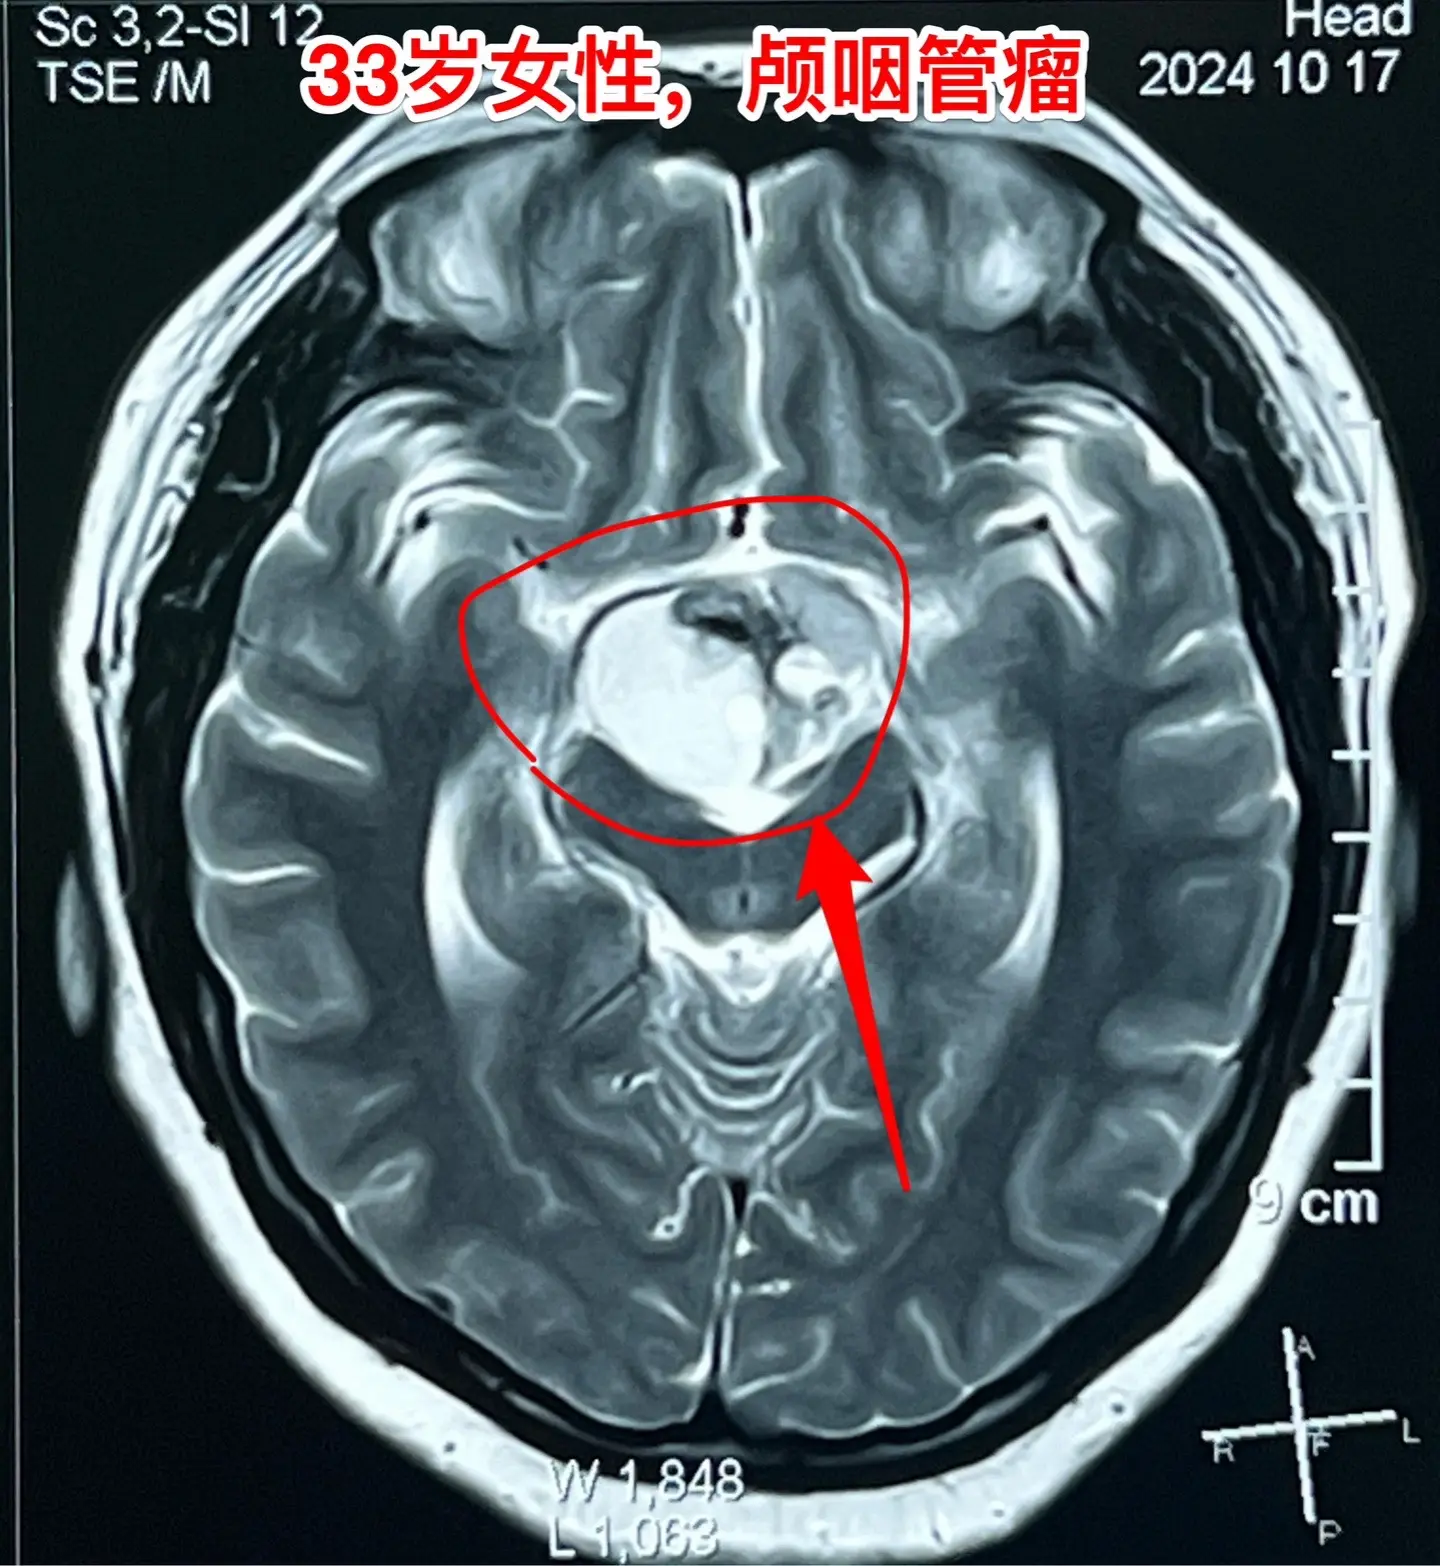

33岁颅咽管瘤患者终于下决心作手术了。洛阳市的女教师,2021年因内分...